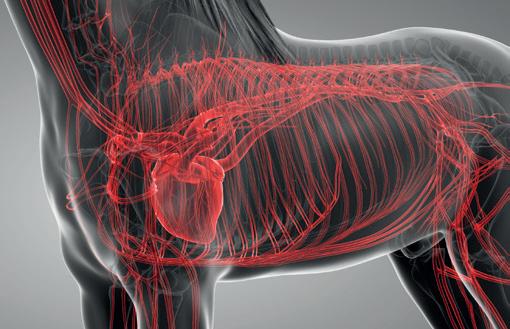

Causes in individual cases may reflect multiple factors, so coming at the issues from several different directions, as is the case with the range of ongoing studies, is a good way to go so long as study subjects and cases are comparable and thoroughly documented. However, starting from the hypothesis that these may all represent basically the same clinical condition, we are approaching the problem from a clinical perspective, which is that cardiac dysfunction is the common cause.

Numerous cardiac disorders and cellular mechanisms have the potential to contribute to transient or complete pump (heart) failure. However, identifying them as potential disease candidates does not specifically identify the role they may have played, if any, in a case of heart failure and in lung hemorrhage; it only means that they are potential primary underlying triggers. It isn't possible for us to be right there when a hemorrhage event occurs, so almost invariably we are left looking at the outcome— the event of interest has passed. These concerns influence the approach we are taking.

• High cardiovascular capacity – allows the average horse to pump roughly a brimming bathtub of blood every minute

At race intensity effort, these mechanisms, and more, have to work in coordination to support performance. There is likely not much reserve left—two furlongs (400m) from the winning post—even in the best of horses. There are many wild cards, from how the horse is feeling on race day to how the race plays out; and in all horses there will be a ceiling to performance. That ceiling—the factor limiting performance—may differ from horse to horse and even from day to day. There’s no guarantee that in any particular competition circumstances will allow the horse to perform within its own limitations. One of these factors involves the left side of the heart, from which blood is driven around the body to the muscles.

The cardiovascular system of the horse exhibits features that help sustain a high cardiac output at peak effort. The feature of concern here is the high exercise pressure in the circulation from the right ventricle, through the lungs to the left ventricle. At intense effort and high heart rates, there is very little time available to fill the left ventricle—sometimes as little as 1/10 of a second; and if the chamber cannot fill properly, it cannot empty properly and cardiac output will fall. The circumstances

required to achieve adequate filling include the readiness of the chamber to relax to accept blood—its ‘stiffness.’ Chamber stiffness increases greatly at exercise, and this stiffened chamber must relax rapidly in order to fill. That relaxation seems not to be sufficient on its own in the horse at high heart rates. Increased filling pressure from the circulation draining the lungs is also required. But there is a weak point: the pulmonary capillaries.

These are tiny vessels conducting blood across the lungs from the pulmonary artery to the pulmonary veins. During this transit, all the gas exchange needed to support exercise takes place. The physiology of other species tells us that the trained lung circulation achieves maximum flow (equivalent to cardiac output) by reducing resistance in those small vessels. This process effectively increases lung blood flow reserve by, among other things, dilating small vessels. Effectively, resistance to the flow of blood through the lungs is minimized. We know this occurs in horses as it does in other species; yet in the horse, blood pressure in the lungs still increases dramatically at exercise.

If this increase is not the result of resistance in the small vessels, it must reflect something else, and that appears to be resistance to flow into the left chamber. This means the entire lung circulation is exposed to the same pressures, including the thin-walled capillaries. Capillaries normally work at quite low pressure, but in the exercising horse, they must tolerate very high pressures. They have thin walls and little between them, and the air exchange sacs in the lung. This makes them vulnerable. It's not surprising they sometimes rupture, resulting in lung hemorrhage.